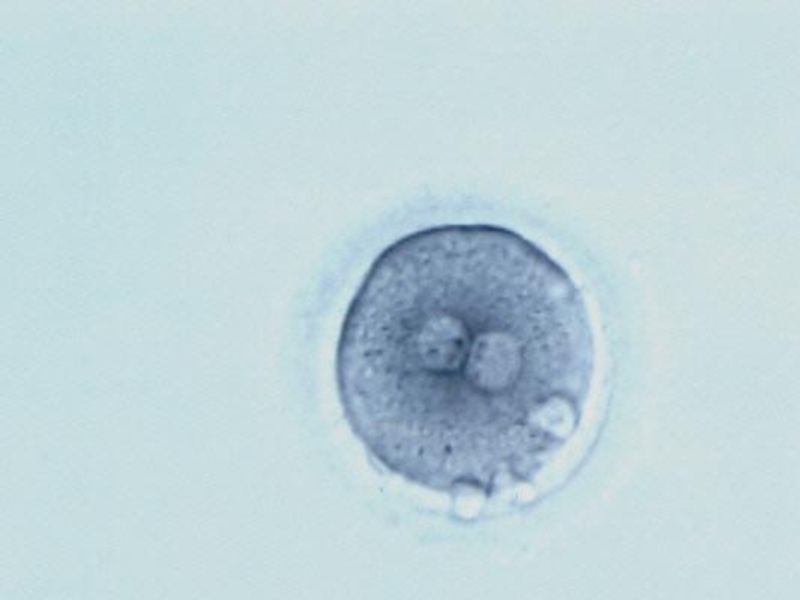

Слайд 7Яичник с фолликулами

Яйцеклетка в

фолликуле

Яичник с фолликуламиЯйцеклетка в фолликуле

В яичниках новорождённой девочки 500000 – 1000000 незрелых половых клеток

К моменту

полового созревания их останется 400000

Созревает только 350-500